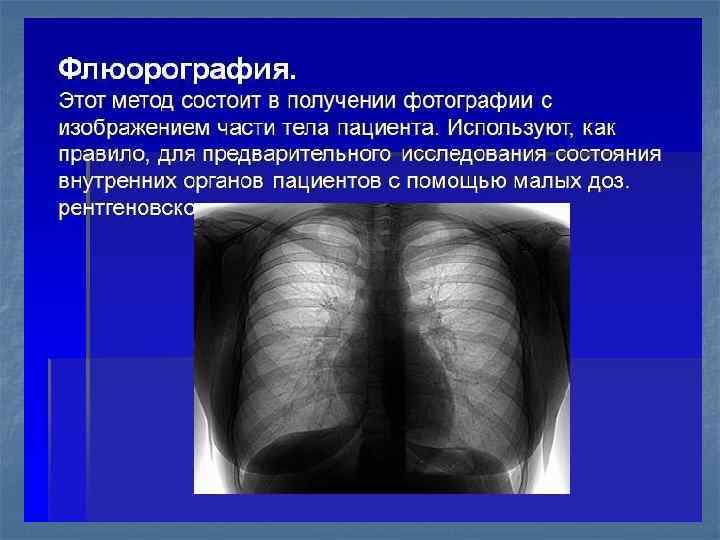

Показания n n n n n Обзор органов брюшной и грудной полости (наличие воздуха, жидкости, метастазов, инородный предметов) Травма костных структур Воспалительный процесс(пазухи черепа, остеомиелит) Дегенеративные изменения позвоночника и суставов Рентген-анатомия органов брюшной полости(желудок, кишечник) Опухоли ЖКТ, легких, реже головного мозга, костей Исследование функций почек и ЖКТ(рентгенография) Аномалии развития органов грудной и брюшной полости (мегоколон, долихосигма, болезнь Гиршпрунга, подковообразная почка, «бычье сердце» и т. п. ) Скрининг заболеваний легких(флюорография)